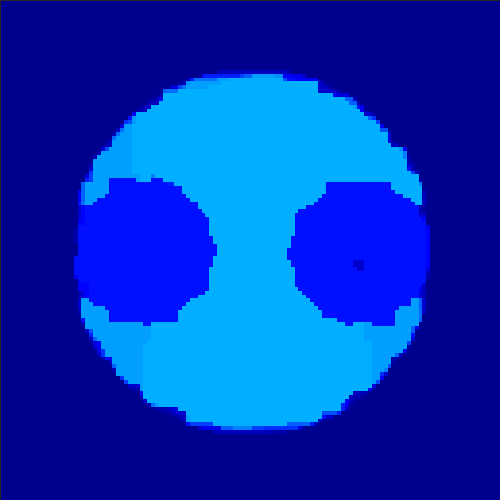

5.2 Monte Carlo Simulation

In order to test the behaviour of the proposed method in a more realistic, random-based test case, we performed a Monte Carlo simulation for dynamic SPECT imaging. First, we created a simple image phantom consisting of an outer and two inner circles which represents the structure of the region of interest (see figure 8(a)). Within those regions we assumed concentration curves over a time period of 90 time steps as displayed in figure 8(b). Based on the tracer intensity in an image frame at each time step, we created a variable number of random decay events (where the number is proportional to the average concentration in one pixel in the whole image frame per time step) with a probability proportional to the concentration in every subregion. They are detected by a virtual double head gamma camera rotating around the patient by 46 degrees per time step, which consists of 374 detector bins. Every simulated decay event is projected onto the scanner and counted by the corresponding detector bin.

In two different tests we fixed the number of events counted by the detector equal to (resp. ) times the average concentration in one pixel. The resulting sinogram images of the accumulated counts in each bin are shown in figure 9.

Based on the sinogram data we applied the proposed algorithm in order to reconstruct the original image sequence. The results for both test cases are shown in figure 10.

As one can see, the method is able to reconstruct the regions properly, even in case of a low count number. Within a number of iterations (average of 100 outer and 10000 inner iterations), the algorithm presents a reasonable reconstruction of the region of interest and the corresponding regional tracer concentration curves. Here, the parameters were not optimized as in the case of the synthesized data sets in the previous section, but kept fixed as , and . With futher optimized parameter values one could possibly provide even better results.